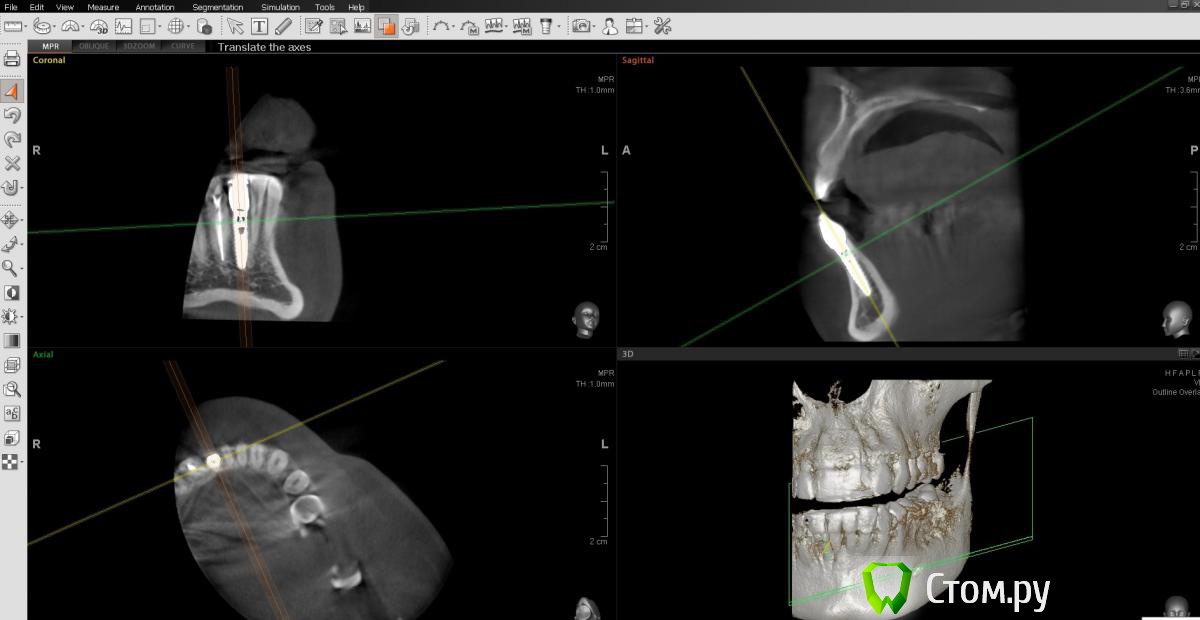

englishlady Опубликовано 6 мая, 2014 Автор Поделиться Опубликовано 6 мая, 2014 http://s019.radikal.ru/i620/1405/43/6a807f37e98f.png[/url] Ссылка на комментарий

englishlady Опубликовано 6 мая, 2014 Автор Поделиться Опубликовано 6 мая, 2014 Еще один срез. Если надо сделать как-то по-другому, постараюсь сделать. Просто последний стоматолог, у которого была, говорил о дополнительном канале.http://i031.radikal.ru/1405/cd/b5f5dd83e07f.png[/url] Ссылка на комментарий

englishlady Опубликовано 9 мая, 2014 Автор Поделиться Опубликовано 9 мая, 2014 Еще КТ. Может можно что-нибудь сказать про дополнительный канал и наличие воспаления.http://i023.radikal.ru/1405/76/586c872dc148.png[/url] Ссылка на комментарий

englishlady Опубликовано 9 мая, 2014 Автор Поделиться Опубликовано 9 мая, 2014 Еще КТ.http://i049.radikal.ru/1405/53/b0585c1cf7cd.png[/url] Ссылка на комментарий